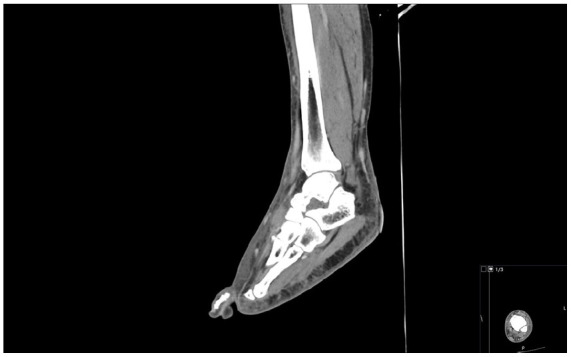

Löfgren's syndrome is an acute, self-limiting variant of sarcoidosis, typically presenting with erythema nodosum, bilateral hilar lymphadenopathy, and acute arthritis or periarthritis-most commonly involving the ankles. Its clinical overlap with other inflammatory conditions can pose a diagnostic challenge. We describe a 34-year-old male with no prior medical history who presented with bilateral ankle and foot pain, erythema, and swelling, initially diagnosed as cellulitis based on imaging findings. He has no response to broad-spectrum antibiotics. During his further hospital stay, he developed polyarthritis. Laboratory evaluation revealed neutrophilic leukocytosis, elevated inflammatory markers, and a normal serum angiotensin-converting enzyme level. Imaging showed bilateral hilar lymphadenopathy and intra-abdominal adenopathy. Bronchoscopy with bronchoalveolar lavage revealed an elevated CD4:CD8 ratio (5.0), and endobronchial ultrasound-guided transbronchial needle aspiration confirmed noncaseating granulomas. Infectious, autoimmune, and malignant causes were excluded. Based on clinical features and histology, a diagnosis of Löfgren's syndrome was established. Nonsteroidal anti-inflammatory drug therapy led to rapid clinical improvement, and antibiotics were discontinued. Löfgren's syndrome should be considered in patients presenting with bilateral lower extremity erythema and swelling unresponsive to antibiotics, especially when accompanied by systemic symptoms. Early thoracic imaging and consideration of sarcoidosis in the differential diagnosis can prevent misdiagnosis and unnecessary treatment.

Abstract Image